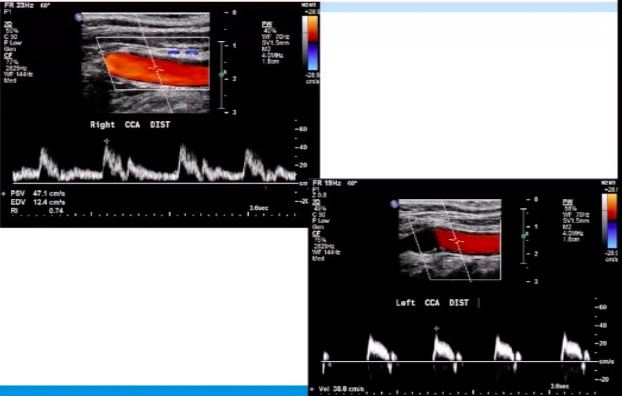

Where should CCA velocity ideally be measured?

a few cm proximal to carotid bifurcation

Carotid DUS images shown below. Diagnosis?

left ICA occlusion

note the externalization* of the left CCA in the DUS image

*occurs when CCA waveform has solely a low-resistance pattern (implies blockage of high-restistance ICA branch)